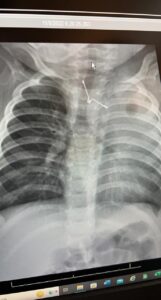

وأكدت أن الفريق الطبي المشرف على الحالة قام على الفور بعمل التحاليل والاشعات اللازمة وإدخال الطفلة لغرفة العمليات بصفه عاجلة وذلك لإكتشاف جسم معدني حاد الاطراف بلعته الطفله وبقي عالقاً في المرىء مسبباً لها مضاعفات صحية خطيرة خصوصاً لو تم تحريكه بأي طريقه خاطئه، حيث نجح الفريق الطبي في مده زمنية تقارب الـ(4)ساعات من اخراج الجسم الغريب بالمنظار وبحذر شديد حتى لا تصاب الأنسجة المحيطة به بأي جروح، وتتمتع المريضة بصحة جيدة تحت العناية المكثفة لإكمال فترة الشفاء.